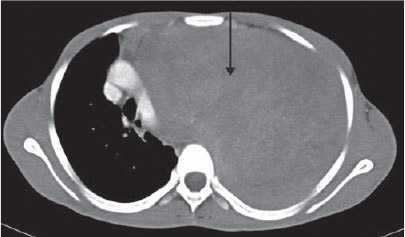

Тупое повреждение крупного сосуда, особенно нисходящей грудной аорты, может быть высоко летальным; при этом ангиография продолжает быть предпочтительным диагностическим методом.14 Компьютерная томография (КТ) и чреспищеводная эхокардиография имеют ограничения, но сохраняют избирательные показания у пострадавших с множественной травмой, чтобы помочь в сортировке.

Многодатчиковая КТ с высокой разрешающей способностью все больше и больше используется для скрининга пациентов с тупым повреждением аорты из-за способности выявлять малые повреждения, а также возможности быстрого сканирования. Данный подход получил весьма противоречивые оценки. Новейшие сканеры часто имеют разрешение, позволяющее видеть то, что ранее не замечалось. Самый важный фактор, вероятно, опыт конкретных клиник в каждой из этих методик. По мере развития, система гарантии качества каждого стационара сможет отследить эффективность каждой из этих методик для конкретной системы.